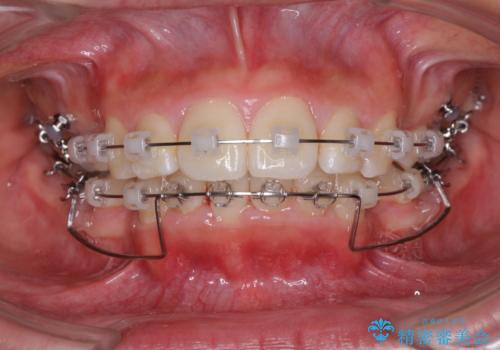

- クリアブラケット

- 治療期間

- 3年

途中で来院されない時期があったため、期間が長引き、更には磨き残しが多かったことで虫歯が多く発現してしまいました。

しっかりと通院するようになってからは順調に治療が進み、横顔の印象が変わるほどスッキリとした口元となりました。